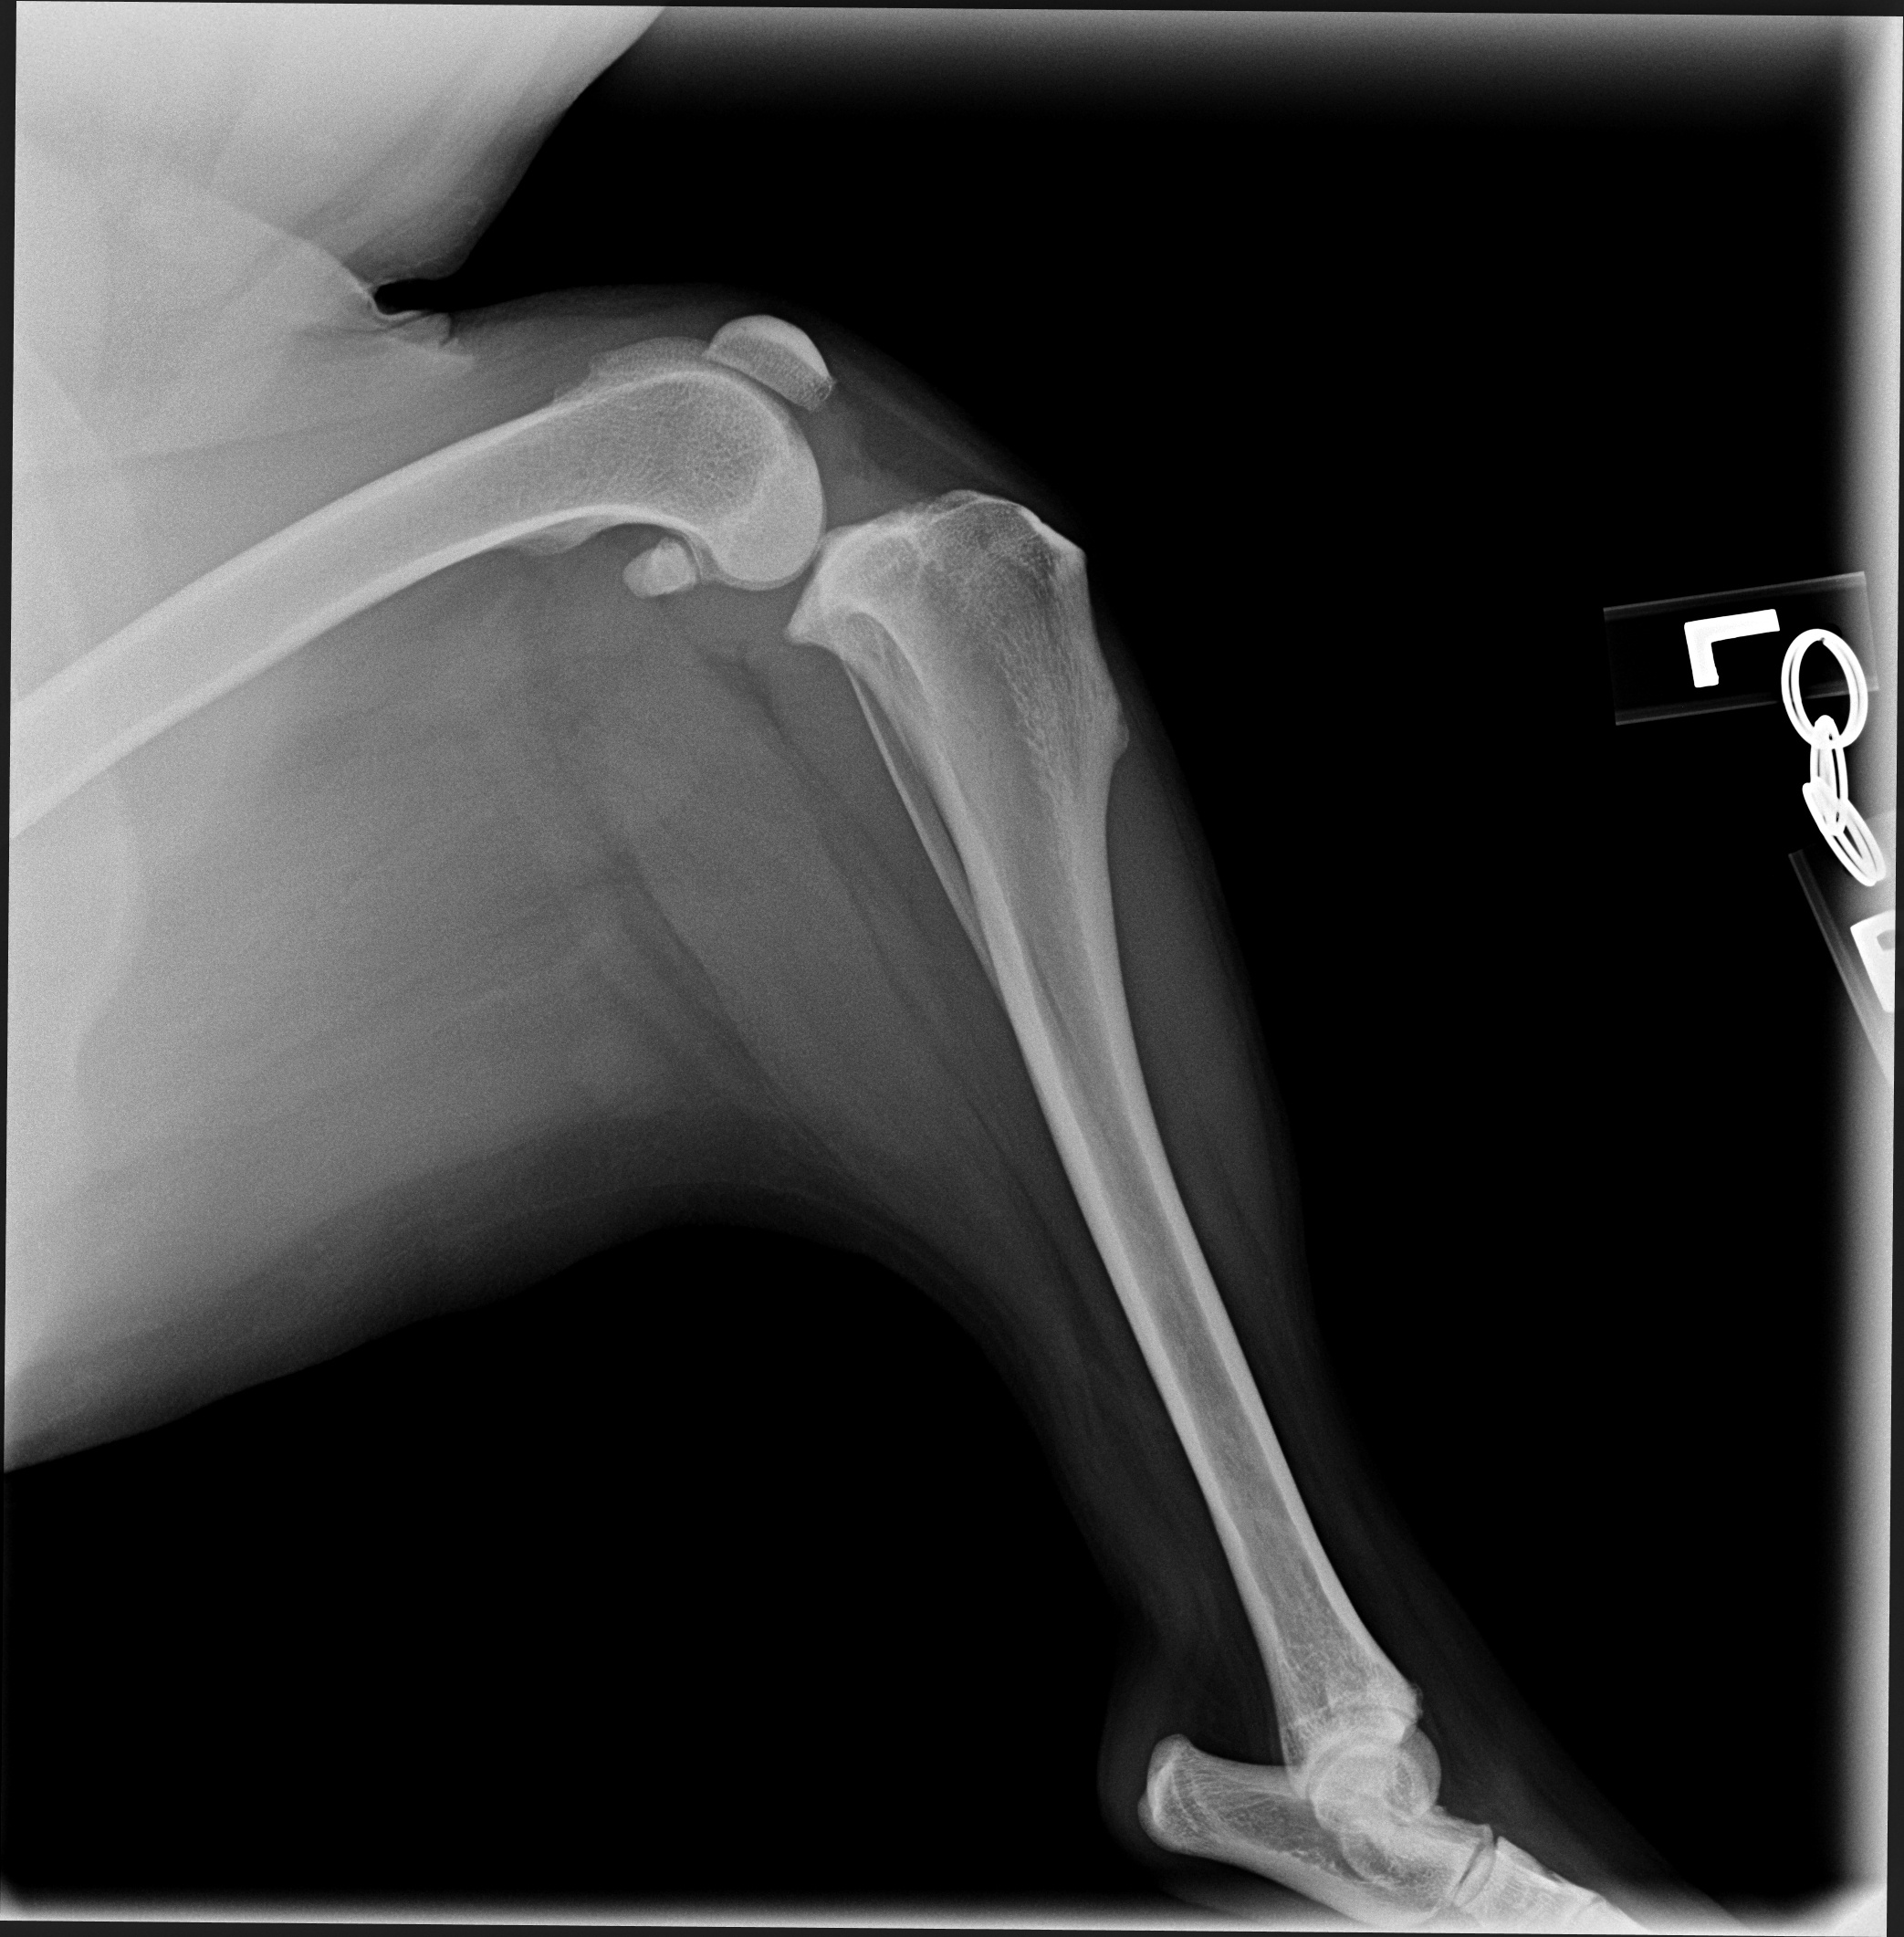

The dataset used for training was collected from various veterinary clinics, as none is available in the public domain, and the objects of interests were manually annotated. The resolution of these images vary largely as they are collected from various sources, thus for the sake of uniformity the images are all scaled to fit the same dimensions. The first part of this project was to develop a lightweight radiograph image sorting algorithm reported in [8]. The images chosen for the task described in this manuscript were all classified to be lateral lower body images by that sorting algorithm. Examples of manual annotations of objects of interests are given in Fig. 4: here regions A, B and C identify the joints while the point ’e’ identifies the centre of Talus and regions d1 and d2 identify the points that form the MTPL.

Most of the source dataset of over a thousand unique knee radiographs were distorted, had poor patient positioning, or were otherwise unfit for annotating. 250 of the original images were of sufficient quality to contribute to this effort. These images were set to have 6 different classes for training purposes, as mentioned and shown in Fig. 4. These were then trained using YOLOv3 [10] and the results of the predicted annotations are shown in Table I. From these predictions the centroids were extracted, which is then used to plot the FTL and MTPL. Then using the method mentioned in Section II, TPA is calculated. Examples of images, the region of interests detection and their respective TPA determination is shown in Fig. 6 and Table I: